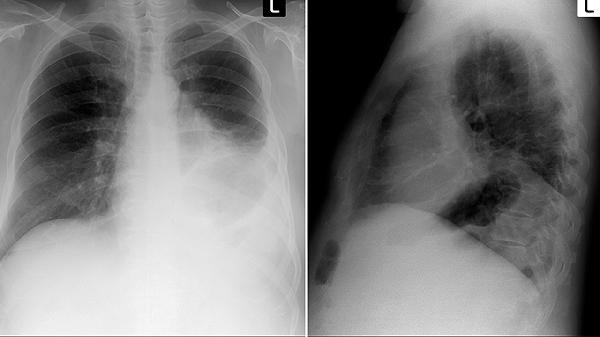

肺动脉分支先天发育不良,或者受到外部肿瘤压迫,都可能造成血管狭窄。CT血管造影有助于明确病变位置,对于局限性狭窄,可以通过支架植入改善血流;如果是广泛的发育问题,则可能需要使用波生坦等靶向药物来降低肺血管阻力。

深静脉血栓脱落并堵塞肺动脉,可能引发慢性血栓栓塞性肺动脉高压。患者多数有下肢静脉曲张或长期卧床史,需要终身抗凝治疗。对于中央型栓塞,可考虑进行肺动脉血栓内膜剥脱术,术后配合康复训练以提升心肺功能。